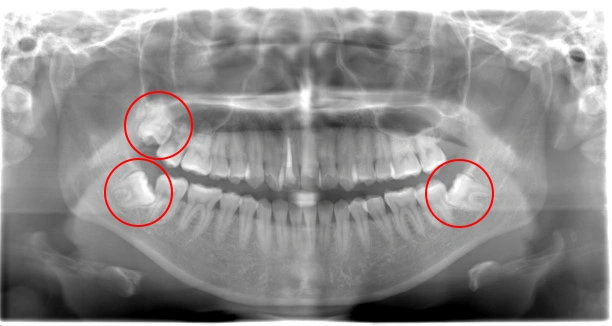

親知らず抜歯 症例①

親知らず抜歯 症例

抜歯中の痛みが心配

4本同時に抜きたい!

難症例で他院に断られた

治療例